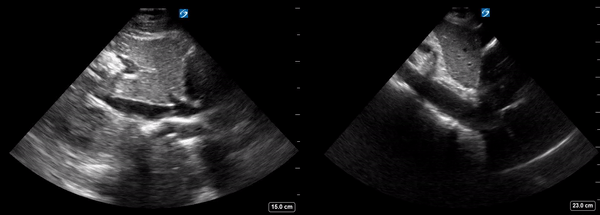

Image 3: Side by side mosaic of IVC (on the Left) and aorta (on the Right)

• Image 1: The Aorta with its characteristic thick hyperechoic (white) walls.

• Image 2: True image of an IVC. Thin walls and traces into the right atrium.